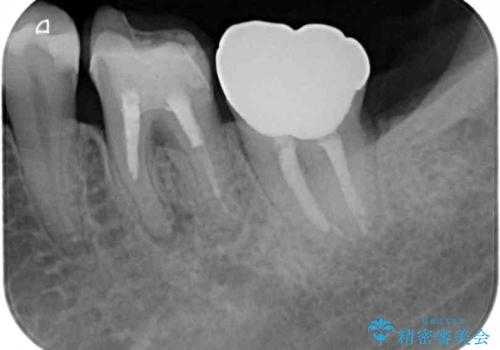

- 奥歯にものが挟まったり引っかかったりすることを気にして来院された患者様です。

詰め物と歯に隙間ができており、既に根管治療をされた歯であったため、フルジルコニアクラウンにて補綴治療をすることとしました。

咬んだときに違和感があるとのことだったので、根管治療を事前におこなうこととしました。

仮歯を装着した時点でものが挟まる症状は改善されました。

根管治療により咬合時の違和感も解消されました。